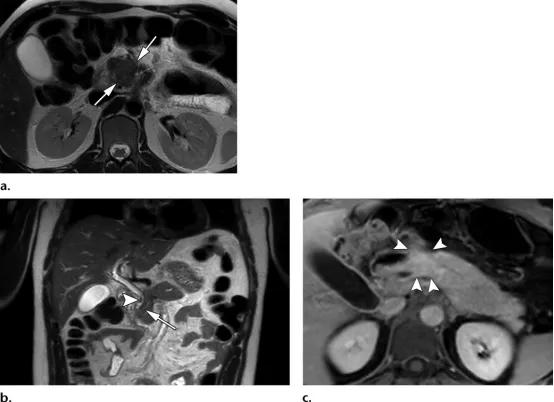

倾向于炎性病变(或肿块形成型胰腺炎),而非胰腺恶性肿物的影像学表现。

(a图)冠状位T2WI磁共振示胰头区域不均匀的肿物样病变(黑色长箭头),主胰管近端管径缩小,但可见横穿此肿物(白色长箭头)。

(b图)磁共振胆胰管成像,清晰显示肿物样病变内狭窄的主胰管(白色长箭头),符合导管穿透征。在胰管远端可见显著的分支胰管(白色短箭头)。